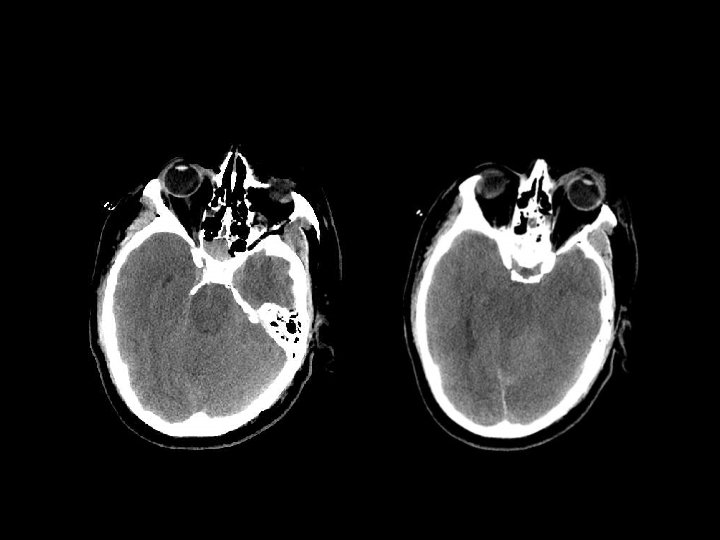

SUBDURAL HEMATOMA n Timbul antara dura dan arachnoid n Dapat melewati sutura n Timbul akibat disrupsi bridging cortical veins n Bentuk konkaf n Hipodens(hiperakut, kronis), isodens(subakut), hiperdens(akut)

W=33 L=41

PENANGANAN SDH n SDH akut dengan ketebalan > 10 mm atau pergeseran midline > 5 mm harus dievakuasi n Pasien yang koma dengan penurunan GCS >2 poin dengan SDH harus menjalani operasi evakuasi